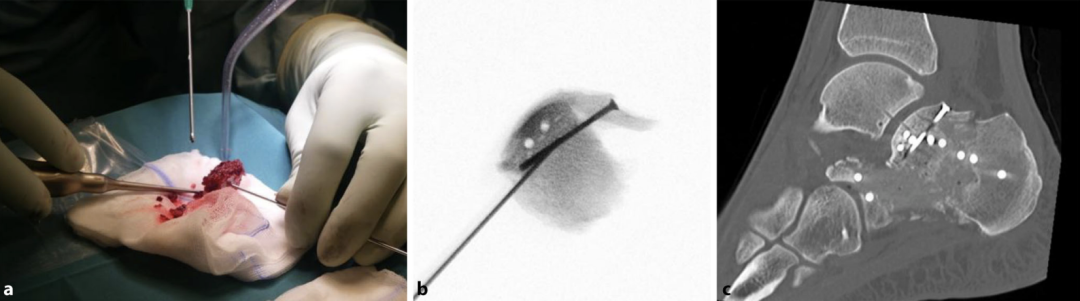

随后,将关节面骨块由内向外逐步贴合恒定骨块进行复位重建,利用细骨撬检查骨块的高度、关节面的对合情况及骨折块的旋转角度是否正常。

采用 1.4mm 或 1.6mm 克氏针进行临时固定,通过侧位透视与Broden位透视检查复位效果,亦可根据需要采用关节镜直接检查关节面的对合情况,在后足内翻应力下可获得充足的关节显露视野。